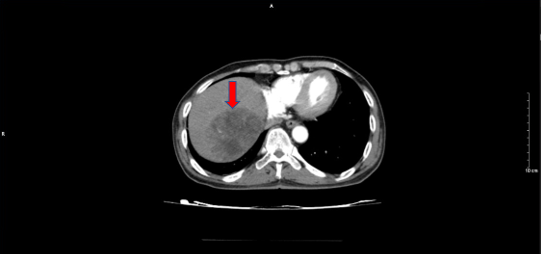

Tháng 11/2023, bệnh nhân đi khám được chụp CT bụng có hình ảnh nhu mô gan hạ phân thùy VIII kích thước 84x70mm ranh giới rõ, ngấm thuốc mạnh không đồng nhất thì tĩnh mạch, thải thuốc thì tĩnh mạch

Hình 3. Khối ngấm thuốc nhu mô gan phải tính chất HCC tăng kích thước nhiều so với phim chụp tháng 9/2023